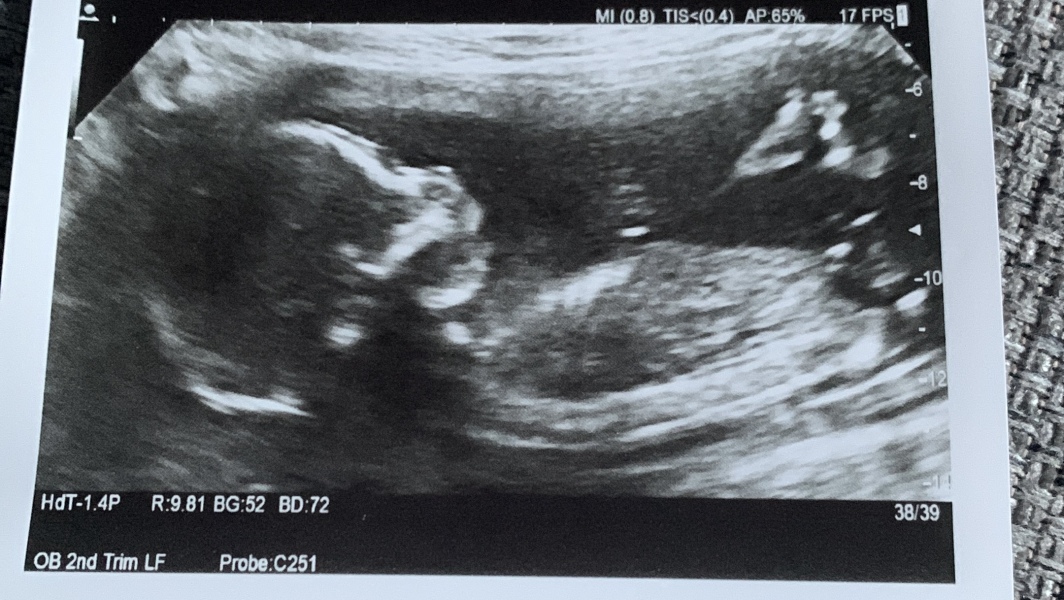

Hi everyone! Hope everyone’s doing ok. Currently on our delayed honeymoon/baby moon and thought I’d do a bit of baby shopping online, but wondered if you all had any thoughts of baby is a boy or girl?! We’re not finding out but I’m secretly so desperate to know and it’s making shopping a lot harder 😂 this was my 20 week scan, we think girl but interested to see what others think

@AGirlsNameIsAryaStark I don't think there's a way to tell from 20 week scans other than looking at their bits - do you have a 12 week scan you could post? I do love a guess at skull/nub theory

@TeddyBeans ah I thought so. I’ve done so much research I’m pretty sure when they measured the legs I saw the 3 lines everyone talks about for a girl but it was so quick! Our 12 week scans weren’t great photos, baby isn’t the most cooperative!

@AGirlsNameIsAryaStark from the 12 week skull I'd be inclined to say a girl. If you saw 3 lines I think you've got a pretty safe bet. Boys are incredibly obvious at 20 weeks, you'd be hard pressed to miss it 😁

Yeah 3 lines on my scan and it’s a girl